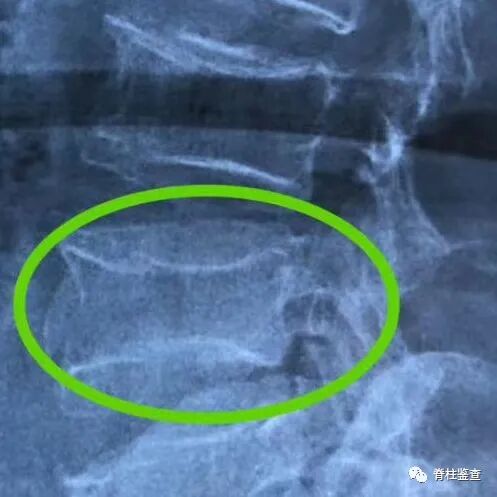

骨质疏松性椎体骨折Kümmell病

骨质疏松性椎体骨折:椎体部分塌陷